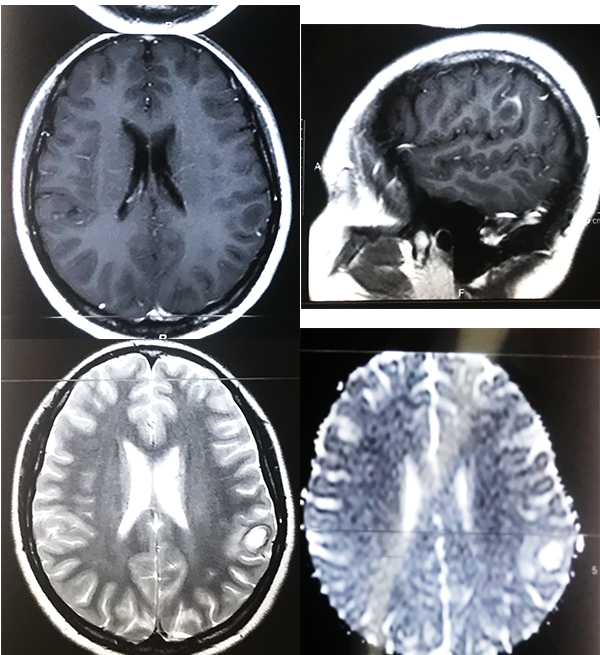

Paciente femenino de 23 años, oriunda de Bolivia, radicada desde hace 5 años en Argentina, dedicada a actividades de agricultura sin aparente nexo con cerdos, quien acude a consultorio externo por presentar cefalea intermitente de moderada intensidad, asociada a hipoestesia de mano derecha. Trae consigo una TC de cerebro simple de 30 días previos al ingreso donde se evidencia a nivel frontoparietal izquierdo lesión ocupante de espacio hipodensa con halo periférico espontáneamente densa y calcificaciones periféricas. Mide aproximadamente 22,5 mm x 16 mm y está asociado a edema de la sustancia blanca periférica, generando efecto de masa local, provocando borramiento de surcos y suturas a dicho nivel; está asociado a colapso pasivo del ventrículo lateral izquierdo (figura 1). RM con contraste visualiza imagen hipointensa en T1, hiperintensa en T2 y restricción en la difusión (figura 2).

Figura 1: TC preoperatoria. A. Corte axial, lesión hipodensa fronto parietal izquierda con halo periférico espontáneamente densa y calcificaciones periféricas, de 22,5 mm x 16 mm con gran edema periférico. B. Corte coronal, visualiza colapso pasivo del ventrículo lateral homolateral a lesión y calcificación periférica del quiste. C. Corte sagital, Lesión subcortical.

Figura 2: RM preoperatoria. A. Corte axial T1, lesión de centro hipointenso con realce periférico. B. Corte sagital en T1 con contraste, se ubica lesión en región postcentral, imagen en anillo C. Corte axial en T2 se visualiza lesión hiperintensa con edema perilesional. D. en difusión se visualiza incremento del coeficiente de difusión aparente.